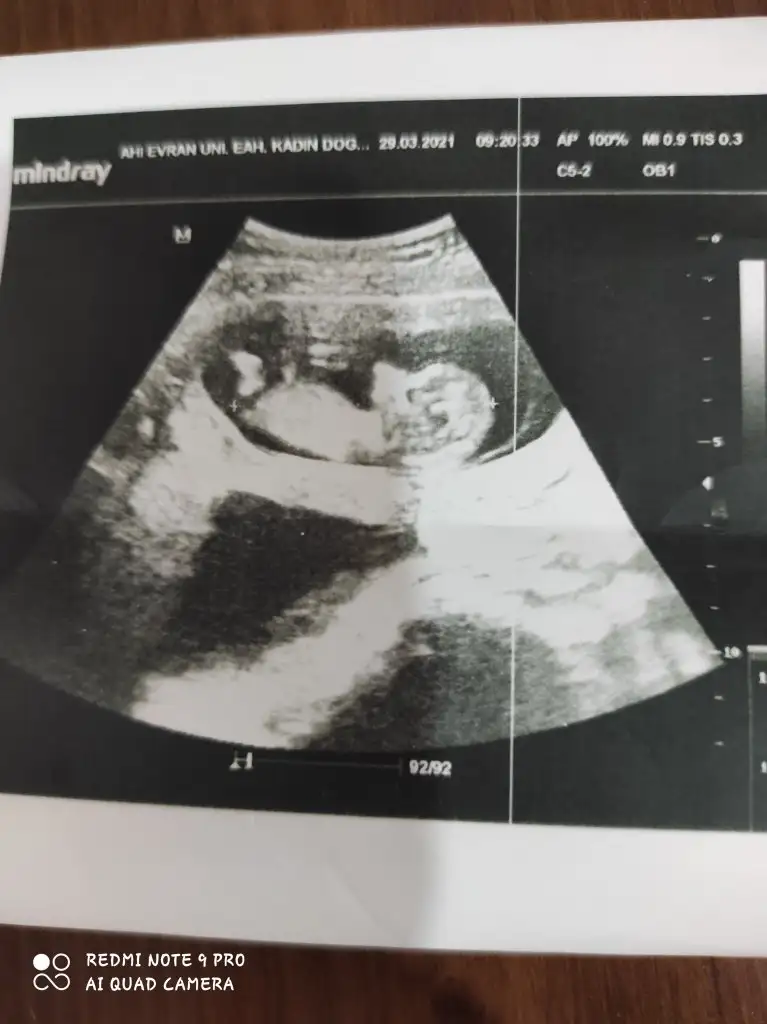

Kız görünüyorIkra meyra 16 haftalık bacak altından sence hangisine yatkın

Sağlıkla gelsin Anketimi oylarsaniz sevinirimTeşekkür ederim evet kızIkra meyra

TabiiSağlıkla gelsin Anketimi oylarsaniz sevinirim![]()